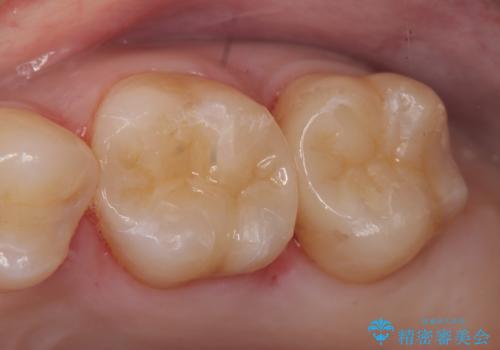

セラミックインレー 下の一番奥歯 歯ぐきの厚みを減らしてぴったりに入れます(ディスタルウェッジ+骨外科)